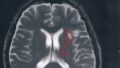

【備忘録】グリオーマ・びまん性星細胞腫:入院6日目(手術当日)

脳腫瘍グリオーマ神経膠腫グレード2覚醒下手術びまん性星細胞腫